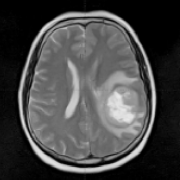

神经胶质瘤 是成人中较常见的原发性恶性脑肿瘤。在美国,恶性神经胶质瘤的年发病率约为5 / 100,000,其中男性略占优势。尽管采用多模式治疗,但预后仍然很差,特别是对于胶质母细...

胶质瘤 是一种原发性脑肿瘤,被认为起源于神经胶质干细胞或祖细胞。根据其组织学外观,传统上将其分为星形细胞瘤、少突胶质细胞瘤或室管膜瘤,并将其划分为WHO I-IV级,以此表示...

胶质瘤医生 说不能手术,可以质子治疗吗?胶质瘤是较常见的原发性脑恶性肿瘤,可以发生在脑内的多种位置。特别是位于手术禁区的脑干、丘脑、脊髓髓内和其它复杂位置的胶质瘤,...